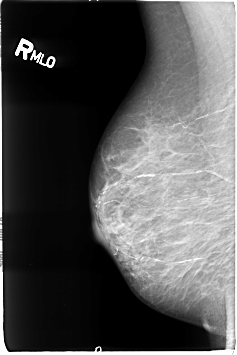

Digital Database for Screening Mammography

Volume: cancer_01 Case: B-3041-1

B_3041_1.RIGHT_MLO

filename B-3041-1

DATE_OF_STUDY 26 1 1996

PATIENT_AGE 75

DENSITY 3

RIGHT_MLO LINES 4608 PIXELS_PER_LINE 3080 BITS_PER_PIXEL 12 RESOLUTION 50 NON_OVERLAY

FILE: B_3041_1.LEFT_MLO.OVERLAY

TOTAL_ABNORMALITIES 1

ABNORMALITY 1

LESION_TYPE CALCIFICATION TYPE PLEOMORPHIC DISTRIBUTION CLUSTERED-LINEAR

LESION_TYPE MASS SHAPE IRREGULAR MARGINS ILL_DEFINED-SPICULATED

ASSESSMENT 5

SUBTLETY 5

PATHOLOGY MALIGNANT